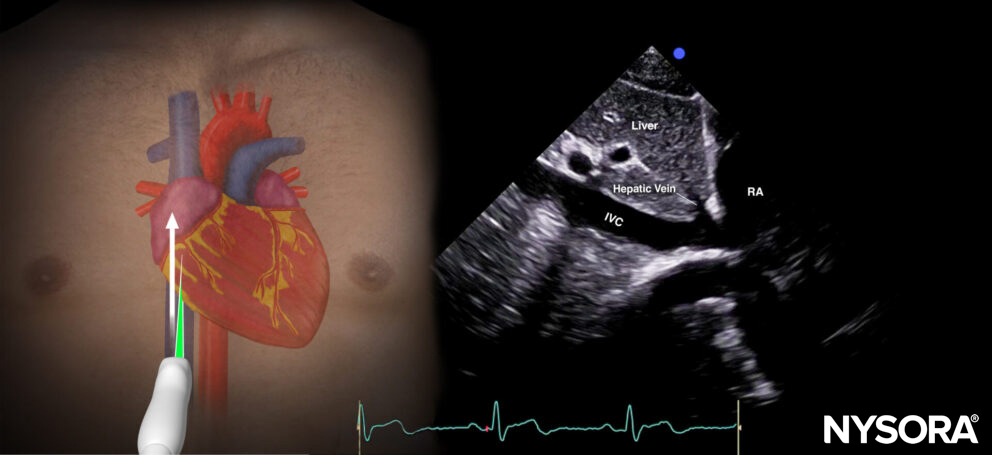

Inferior vena cava view (IVC)

Transducer position and sonoanatomy of the inferior vena cava view.